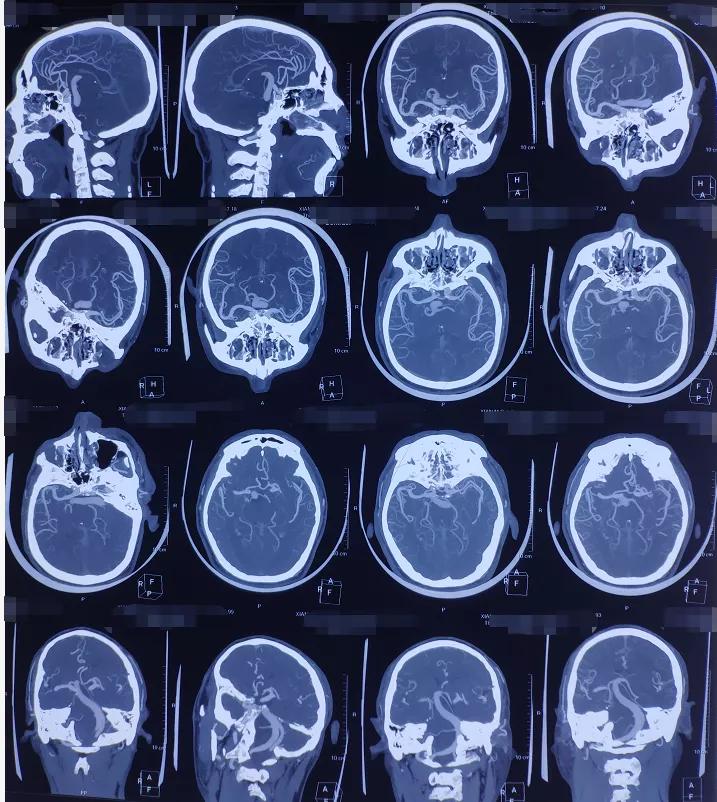

术前影像学检查: